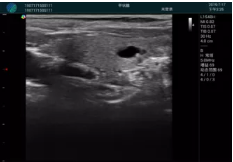

腺體內(nèi)部清晰顯示一低回聲塊影,形態(tài)不規(guī)則,邊界模糊,邊緣呈毛刺狀,內(nèi)部見砂礫樣鈣化

M20引導(dǎo)下穿刺活檢術(shù)

M20引導(dǎo)下平面內(nèi)穿刺取出的腫塊組織